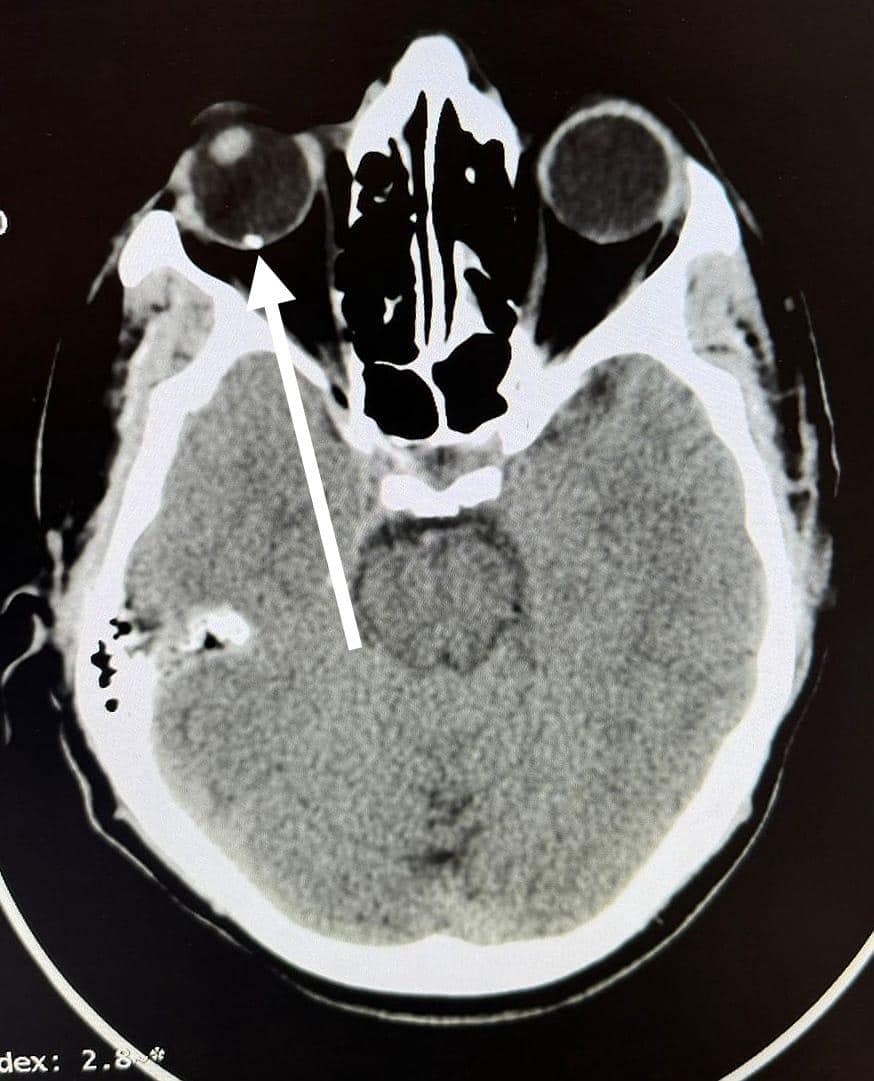

ومن جانبه أوضح الدكتور مجدي القاضي عميد كلية الطب البشري، أن قسم الطوارئ بالمستشفي الجامعي استقبل “عامل” يعمل في تقطيع الحديد بالصاروخ بدون استخدام اي وسائل حماية مما أدي الي دخول “شظية” اخترقت جميع طبقات العين وتسببت في تهتك في القرنية والعدسة والجسم الزجاجي لتستقر في الشبكية، مشيراً الي ان المستشفي الجامعي تعد القبلة الاولي التي يقصدها جميع حالات الطوارئ من كافة الجهات وعلي مدار ٢٤ ساعة بالمجان علي نفقة الدولة او الخاضعين لمظلة التأمين الصحي.

ومن جانبه قال الدكتور محمود فاروق استاذ الشبكية، أن الفريق المعالج نجح إجراء عملية دقيقة اسفرت عن استئصال الجسم الزجاجي، و الوصول الي قاع العين لإزالة الجسم الغريب وعمل كي للشبكية “بالليزر” لتجنب حدوث إنفصال شبكي وتم انقاذ عين المريض من العمي المحقق.